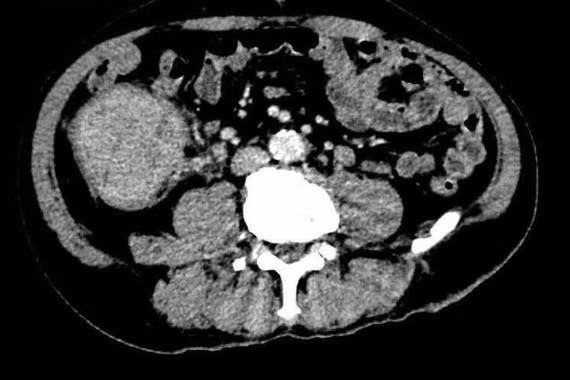

Dưới sự chỉ đạo của BS.CKII Ông Huy Thanh, các bác sĩ khoa Hồi sức và Tiêu hóa đã phối hợp cùng ê-kíp nội soi từ Bệnh viện Đa khoa Trung ương Cần Thơ tiến hành hội chẩn khẩn cấp. Bé được thực hiện nội soi tiêu hóa để xác định và cầm điểm chảy máu.

Nhờ sự phối hợp nhịp nhàng của đội ngũ y bác sĩ, điểm chảy máu đã được kiểm soát thành công. Sau can thiệp, bé dần ổn định, không còn tiêu máu thêm, các dấu hiệu sinh tồn cải thiện rõ rệt – mạch: 100 lần/phút, huyết áp: 122/70 mmHg, nhiệt độ: 37,2°C, Hct: 36%.